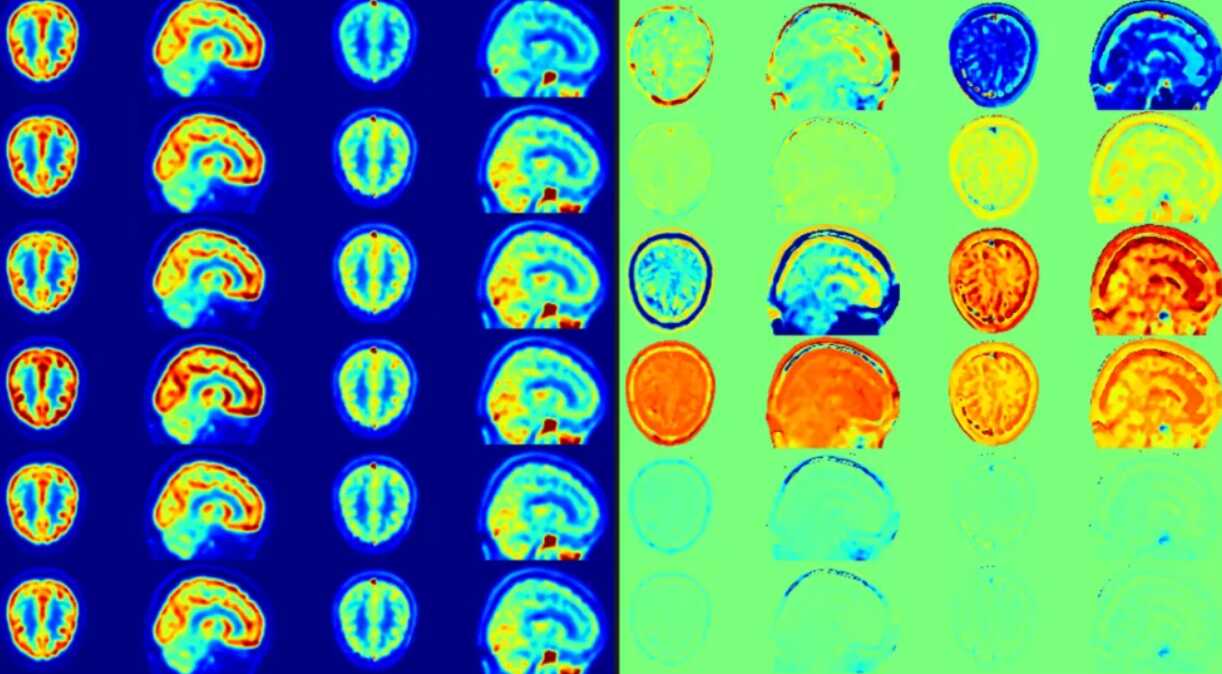

PNAS | 定量解构肿瘤微环境:DeSide助力多种肿瘤内细胞丰度的精准预测

肿瘤微环境是一个由多种类型细胞组成的复杂生态系统。在现有的技术中,流式细胞术和单细胞RNA测序(scRNA-seq)等实验方法能够直接测定肿瘤微环境中的细胞比例,但这些方法通常成本较高。

肿瘤微环境是一个由多种类型细胞组成的复杂生态系统。实体肿瘤内,除了癌细胞之外,还存在数量可观的血管内皮细胞、成纤维细胞、以及多种免疫细胞,如肿瘤相关巨噬细胞和肿瘤浸润淋巴细胞等。大量研究表明,这些不同类型细胞的比例,在多种癌症类型中与患者的病情进展密切相关。因此,精...